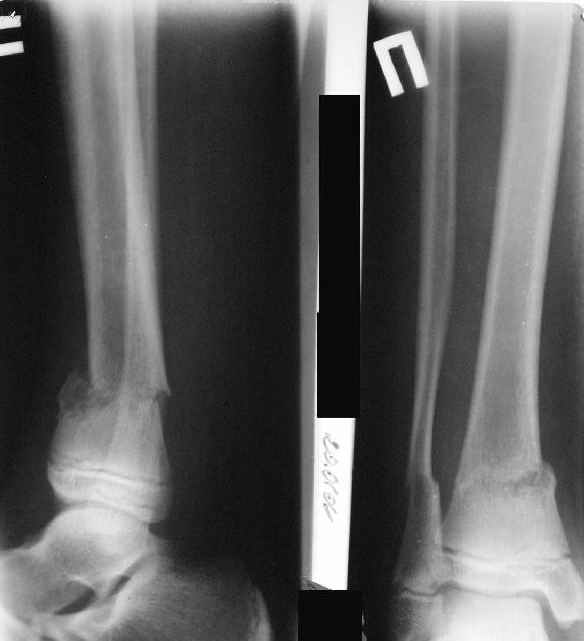

Скелетное вытяжение за пяточную кость.

В первые сутки значительный отек с\3, н\3голени, стопы с развитием практически неуловимого в нашей стране ;) компартмент синдрома (фасциотомии не проводилось), недочеты по укладке на скелетном

вытяжении.

A> Скелетное вытяжение за пяточную кость.

A> В первые сутки значительный отек с\3, н\3голени, стопы с развитием

A> практически неуловимого в нашей стране ;) компартмент синдрома

A> (фасциотомии не проводилось),

А вы как уловили? По развившемуся некрозу кожи?

A> недочеты по укладке на скелетном

A> вытяжении.

A> На вытяжении около 8 нед, в дальнейшем в гипсовых повязках ~ 8 мес.

Вытяжение

|